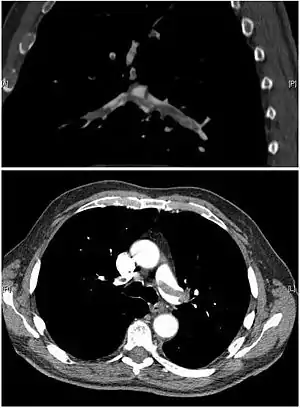

تصوير طبقي محوسب

التصوير الطبقي المحوسب للرئة والمصحوب باستخدام الصبغة المشعة في الوريد أصبح واسع الانتشار والاستخدام في تشخيص المرضى المشتبه بإصابتهم بالانصمام الرئوي، لهذا النوع من التصوير حساسية تبلغ 83% ودقة نوعية تصل إلى 96%.[39][40]